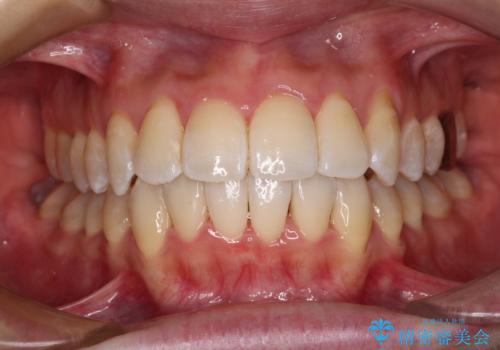

狭い上顎骨を拡大 著しい叢生を抜歯矯正で改善

治療途中、長期間海外旅行をされたり、帰国後には遠方へ転居されたりと、治療期間が伸びましたが、2年強で治療を終えることができました。